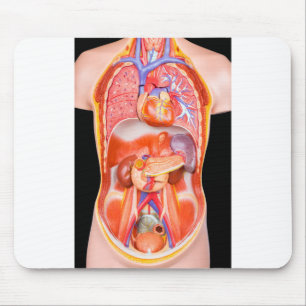

Kroppsmodell hos människa med organ vykort

Pris21,00 kr

Kroppsmodell hos människa med organ anteckningsblock

Pris150,00 kr

Kroppsmodell hos människa med organ vykort

Pris21,00 kr